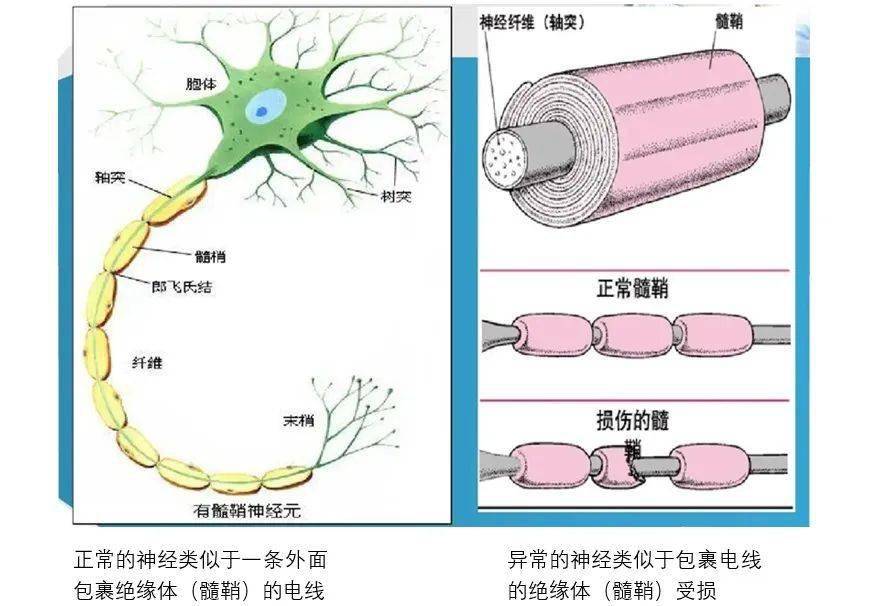

髓鞘是包裹在神经纤维外的细胞膜,通俗一点讲有点类似于包裹在电线外